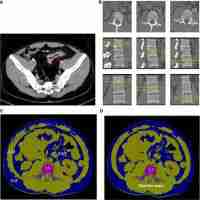

| Abstract | Background To investigate the value of quantitative computed tomography (QCT) measurement of bone mineral density (BMD) in middle-aged and elderly men with abnormal blood glucose. Methods Total 138 men aged above 50 years old with routine physical examination were involved in the study. All participants were evaluated with serological index, BMD by QCT and dual energy X-ray absorptiometry (DXA). Statistical analysis was conducted by χ2 test and regression model. Results All individuals were divided into normal blood glucose (NBG) group and abnormal blood glucose (ABG) group. Compared with NBG group, BMD detected by QCT was obviously lower in ABG group (P < 0.05). More cases with low bone mass or osteoporosis were detected by QCT measurement than DXA (χ2 = 56.618, P = 0.000), which were consistent in both NBG and ABG groups (χ2 was 33.564 and 23.250, P = 0.000). No significant difference of detection rates was found in both subgroups neither by QCT nor DXA measurement (χ2 = 4.204, P = 0.122). Regression analysis revealed that ABG was negatively associated with BMD assessed by QCT (β = -0.217, P < 0.05), which did not show statistical difference after adjusting for age. Conclusion In middle-aged and elderly male patients with NBG or ABG, QCT manifests higher detection rates of low bone mass and osteoporosis than DXA. ABG is negatively correlated with BMD measured by QCT, which is affected by age. |